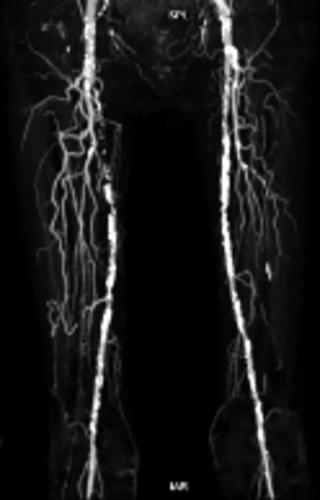

主訴は間欠性跛行(Rutherford3)、リスクファクターは糖尿病と高血圧、既往歴は関節リウマチ、ABIは左0.57、右は測定不能であった。今回のターゲットリージョンは左SFAとし、左PTA(Posterior Tibial Artery)からシース挿入をするとBTK3枝閉塞のリスクがあるので、左 DA(Dorsal Artery)からTAIの方針とした。

同側順行アプローチにて造影を行うと前回治療したPA(Peroneal Artery)は開存しており、ATA(Anterior Tibial Artery)は入口部から閉塞していた(図1)。末梢部分のDA(Dorsal Artery)は確認出来た(図2)。